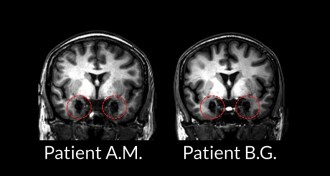

Immune system gene leads to schizophrenia clue

Excessive snipping of nerve cell connections may contribute to schizophrenia.